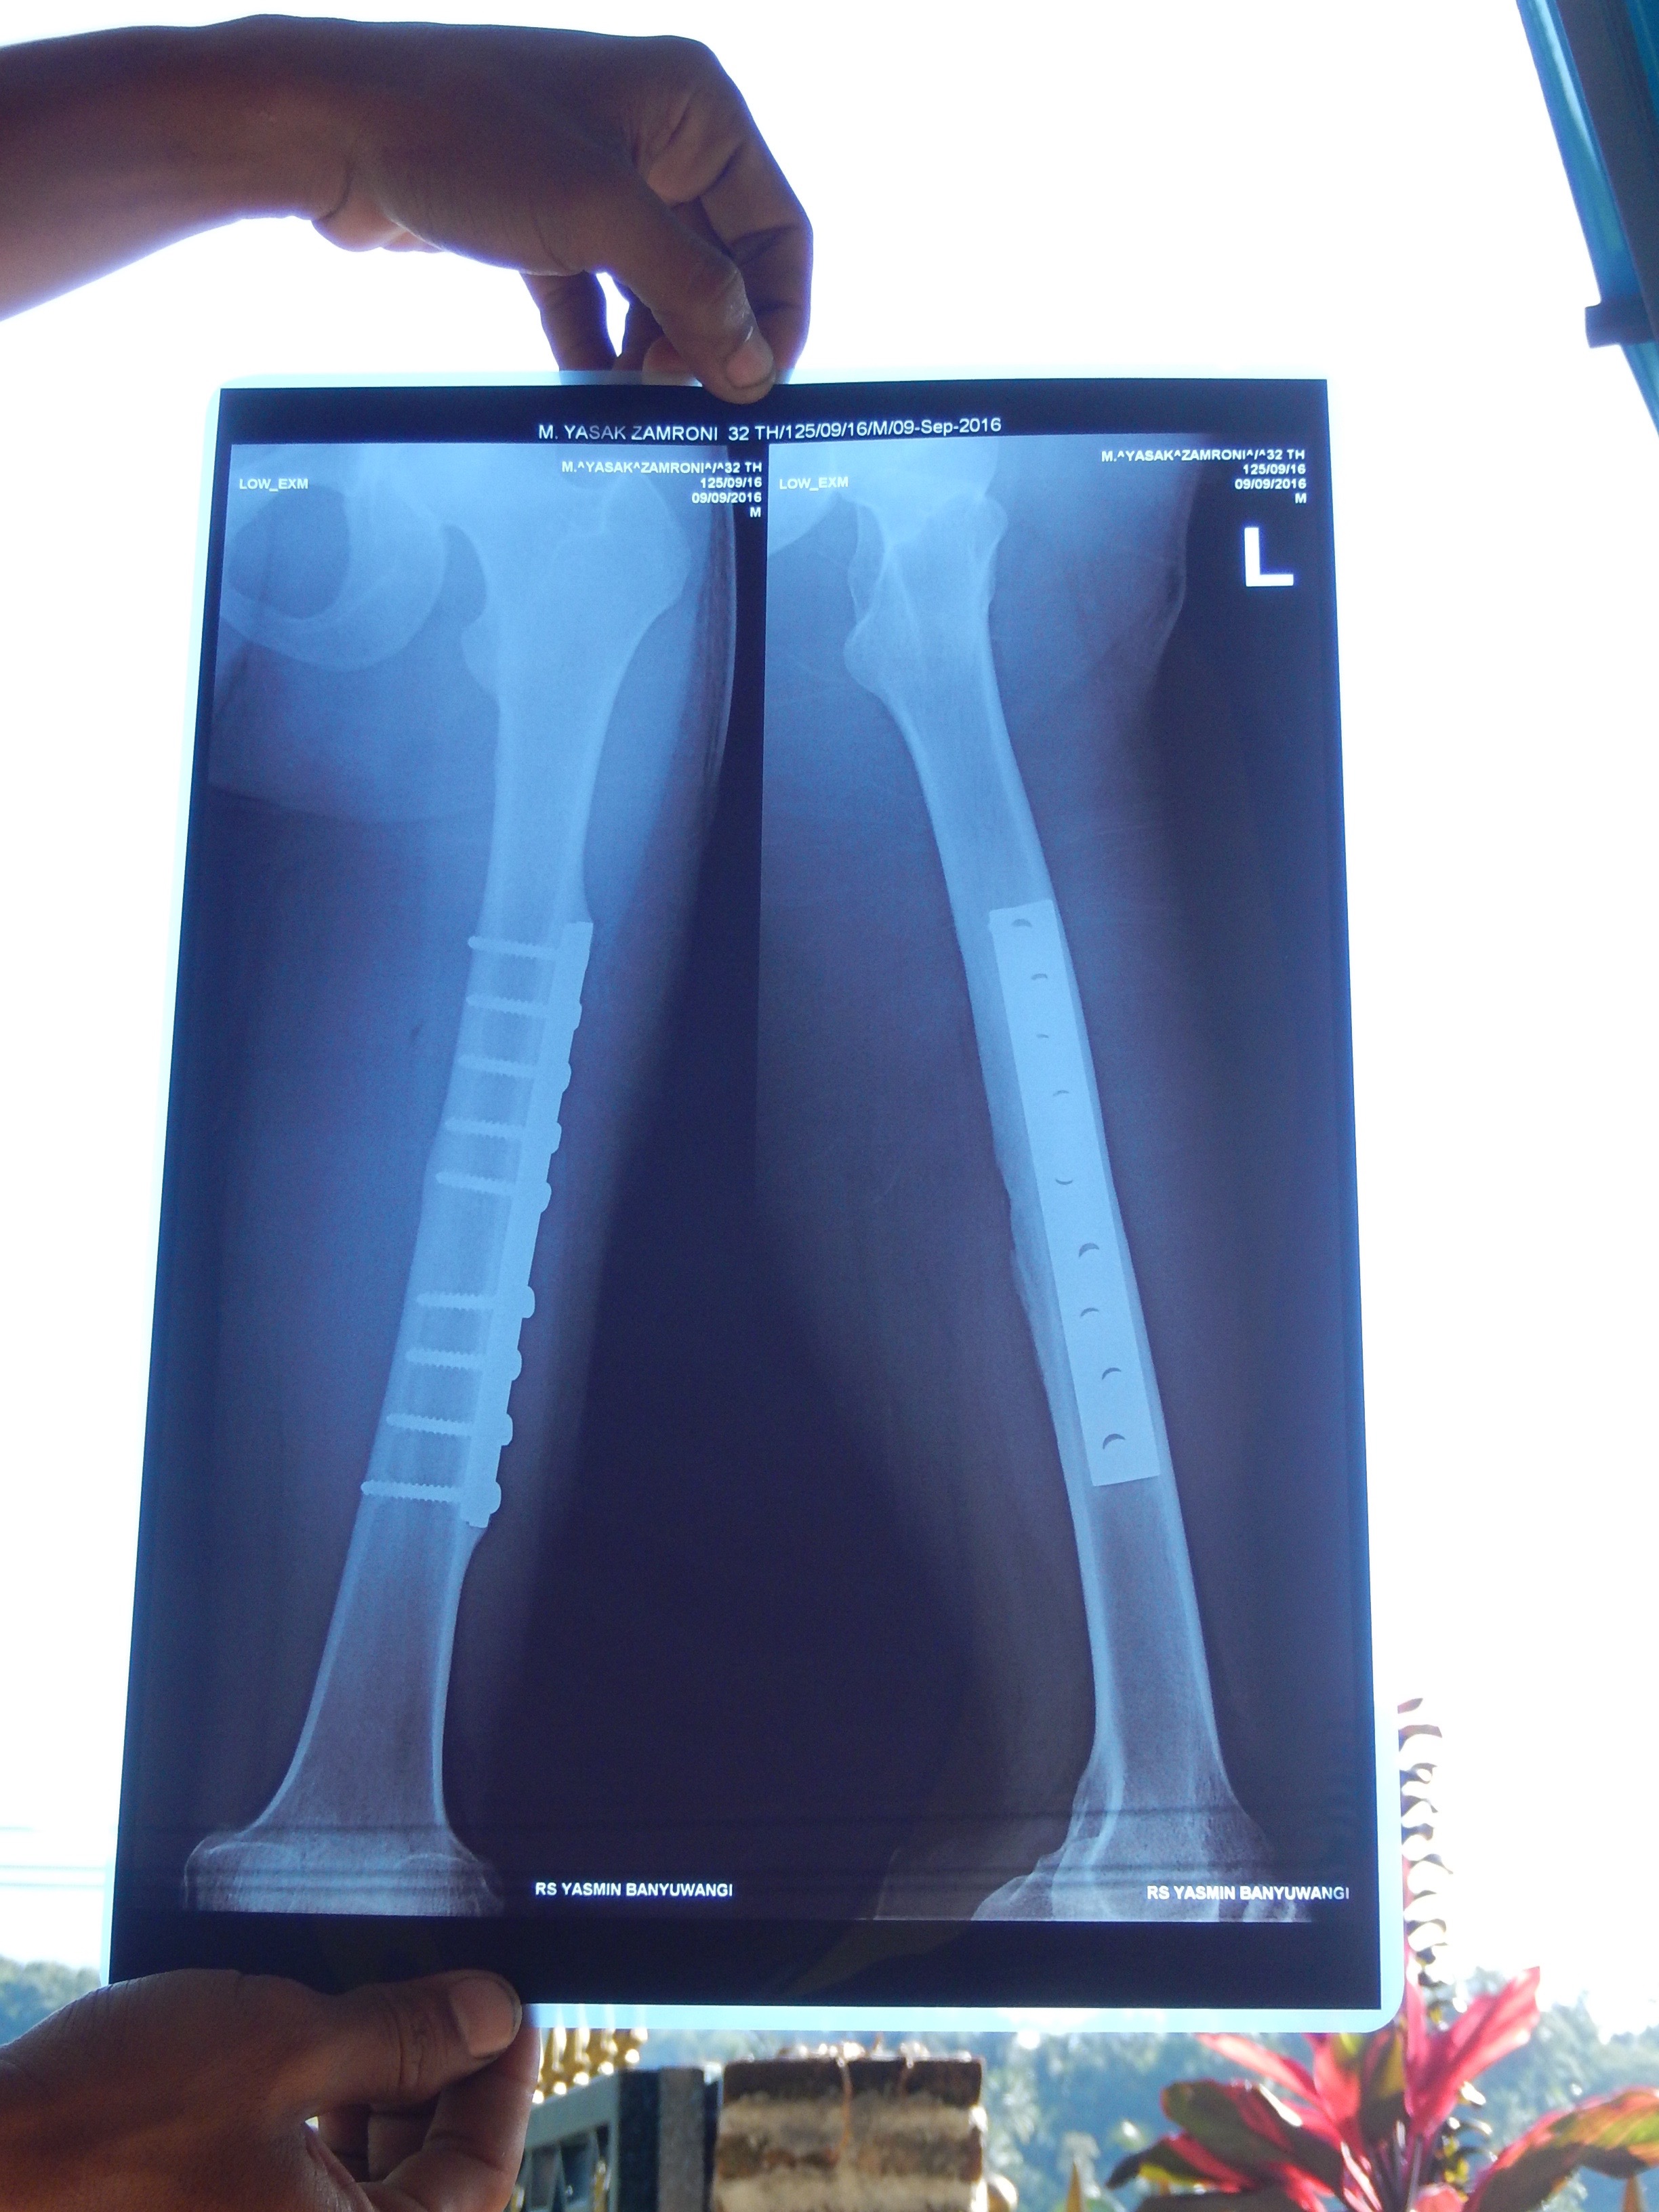

Das Corpus Delicti im Lichte der Röntgenstrahlen, gehalten vom Inhaber des Beines Yusek

Nach Röntgenbild ist der Knochen gut zusammengewachsen. Der Junge hat gute Konstitution. Der OP steht nichts im Wege. Er hätte noch heute unters Messer gehen können, doch ist morgen eine Familienfeier, und so wird er sich nächsten Dienstag operieren lassen.

Das Metallteil ist mittels neun 3cm langen Schrauben mit dem Knochen verbunden. Morgen bei Sonnenlicht werde ich das Röntgenbild fotografieren und oben in den Artikel reinhängen.